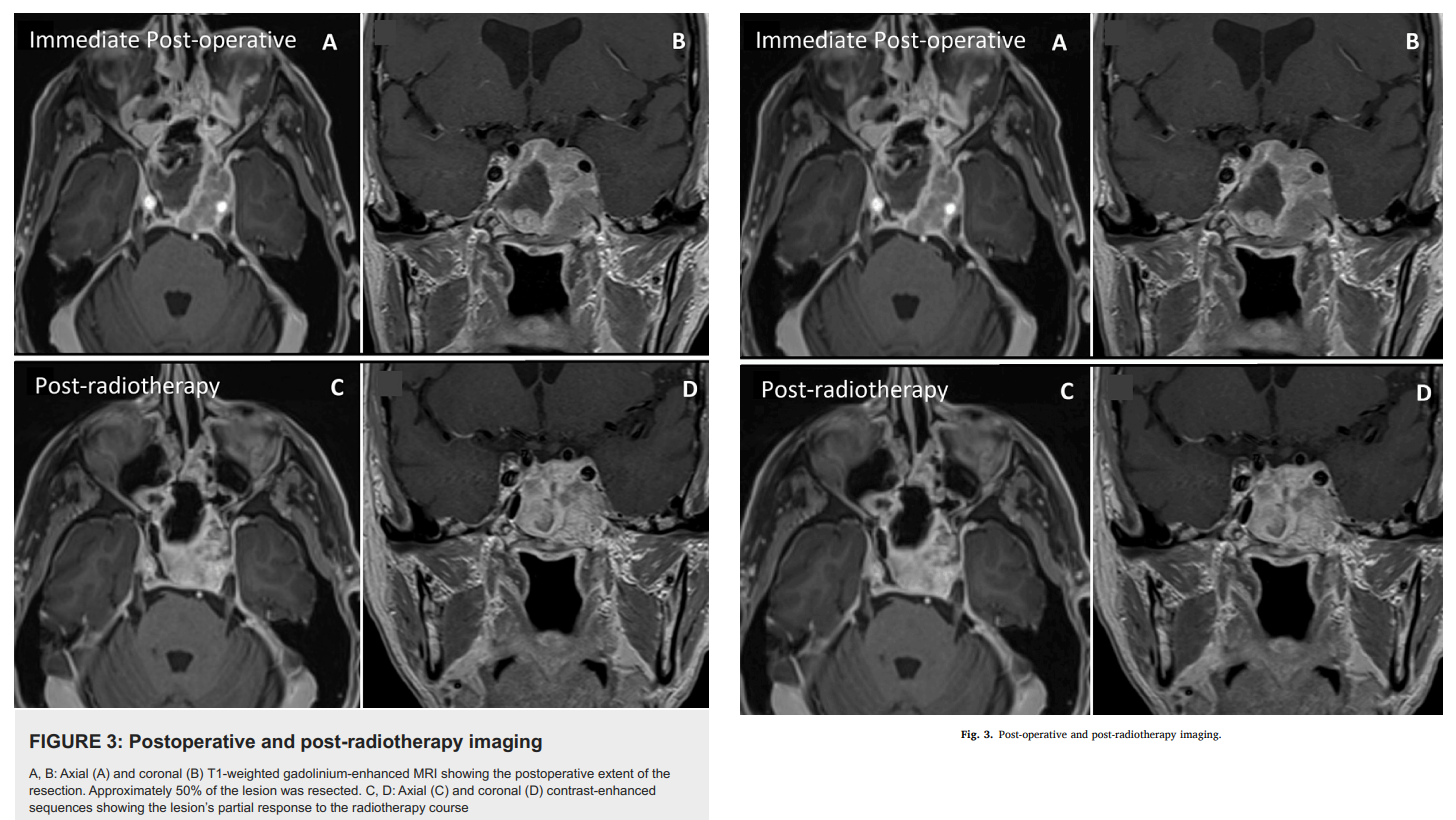

Stephenson does in fact have a neurosurgery publication trail. Behold “Metastatic Seeding From a Gastrointestinal Neoplasia in a Pituitary Adenoma: A Case Report and Literature Review” (Gariépy & Champagne, 2023) – presenting a rare turducken of a tumor. Those authors chose to publish at Cureus. Now it happens that Cureus trust Stephenson with peer-review responsibilities (believing his claim to have expertise in Neurological Surgery, from Feinberg School of Medicine this time), which gave him early access to the Gariépy / Champagne manuscript. So it comes as no surprise that the manuscript reappeared in Elsevier, with the text lightly rephrased but with the same MRI scans.

Matthew Stephenson Adenoma replacement due to invasion of a metastatic Mass: A case report and literature review Interdisciplinary Neurosurgery (2023) doi: 10.1016/j.inat.2023.101748

Stephenson explained in PubPeer comments that his version of the case-study wasn’t stolen, because the qualified neurosurgeons misidentified the tumor (according to his interpretation of their observations) – so he is entitled to swipe their images, clinical description and literature review, and present them as his own. The editors of Interdisciplinary Neurosurgery have been informed.